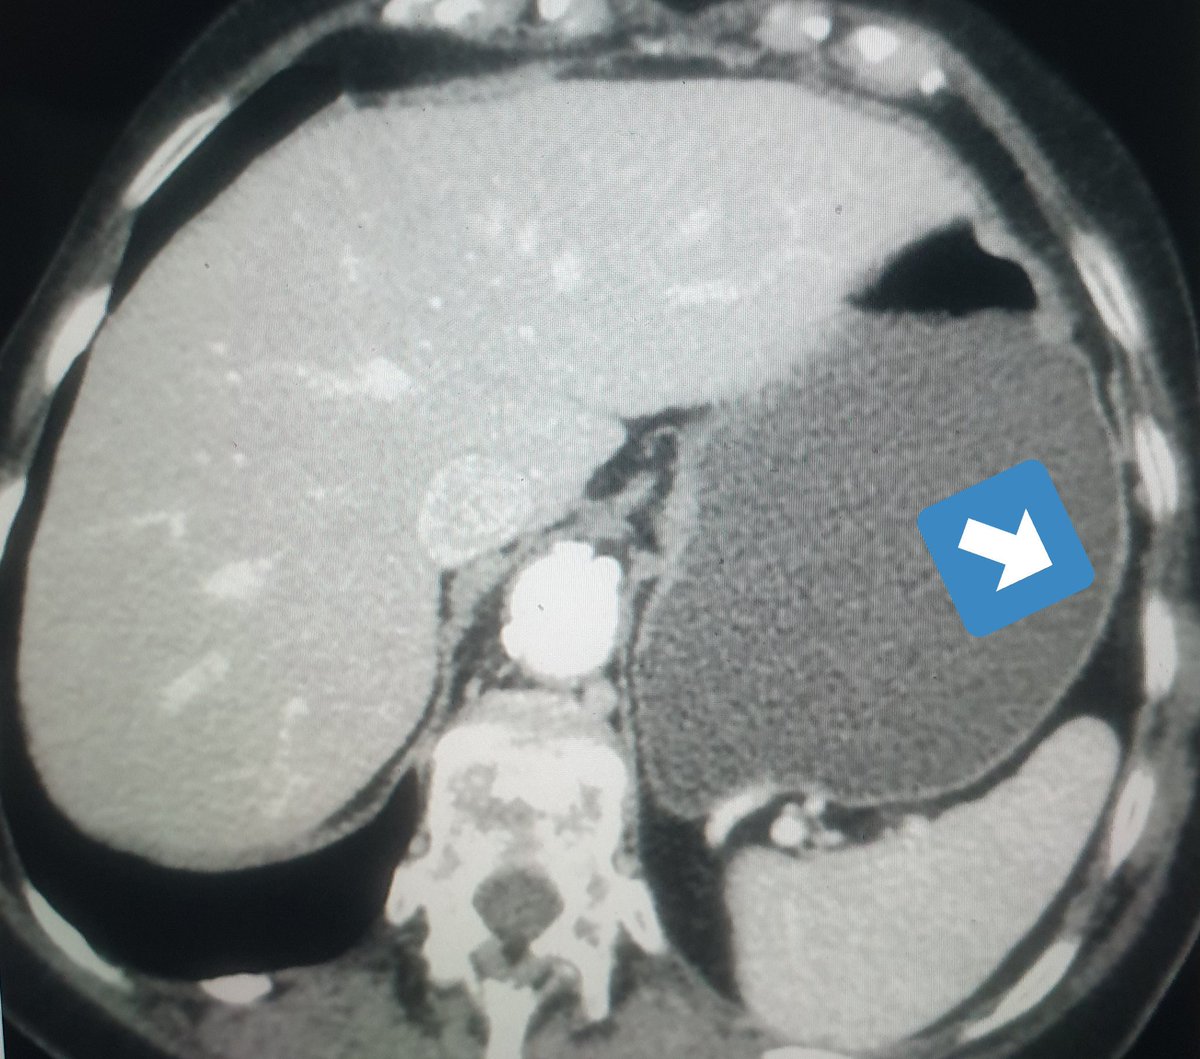

One known indication also is lymphoma or metastasis